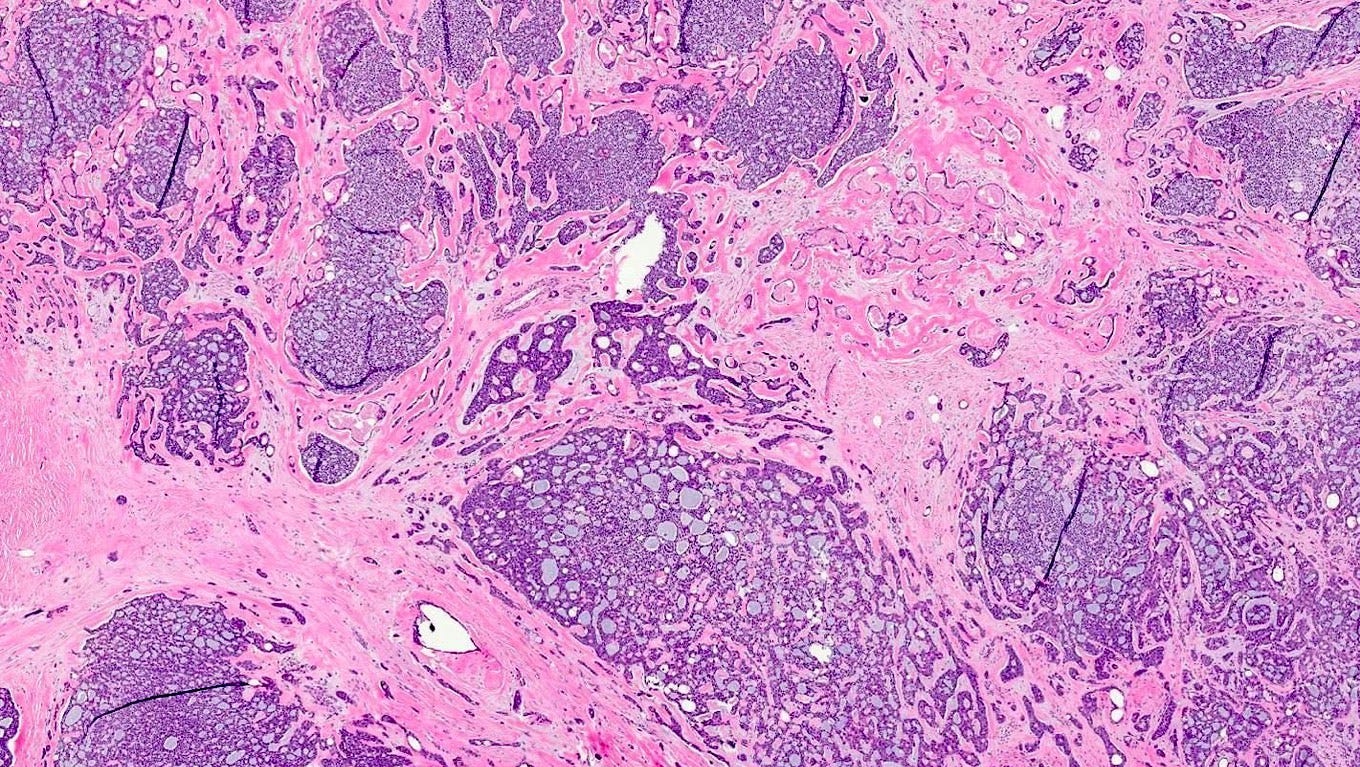

Adenoid cystic carcinoma of the breast - microscopic and cytologic images

Microscopically, adenoid cystic carcinoma of the breast is characterized by a biphasic cellular pattern of luminal epithelial and basaloid myoepithelial cells. The tumor exhibits cribriform, tubular and solid growth patterns, with pseudocystic spaces filled with basophilic mucinous material. Perineural invasion is less common in the breast, distinguishing it from its salivary gland counterpart.

Grossly, adenoid cystic carcinoma of the breast typically presents as a 1 - 3 cm, well circumscribed, firm mass.